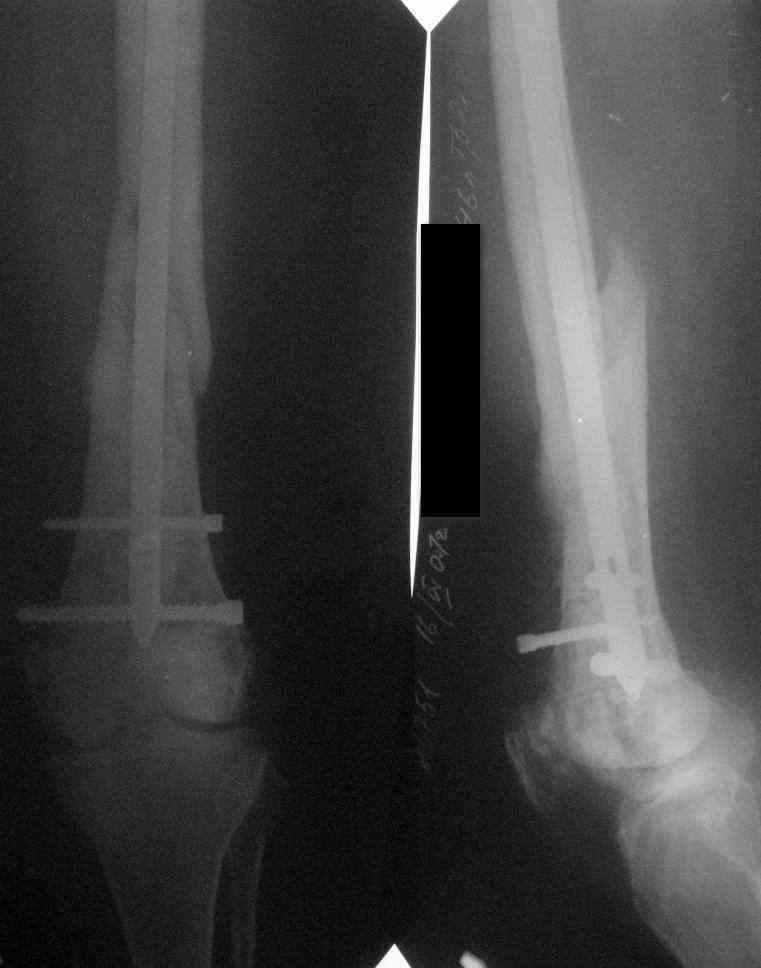

Выполнили операцию по сохранению опорной конечности Начало см. здесь.

В связи с проблемами снабжения операция выполнена в два этапа.1. некрэктомия, операционная биопсия. Резекцию концов отломков ни производили, их костная плотность не изменена. Почистили канал, промыли, ушились. 2. Пломбировка дистального отломка цементом, синтез сплошным титановым гвоздем. Гвоздь подобрали максимально возможный 12 мм, рассверлили дистальное отверстие для винта 6.5мм. Приготовили пробку из цемента с антибиотиком ванкомицином(примерно 0.5г на 20г цемента). Дождавшись пластилиновой консистеции цемента установили пробку в канал дистального отломка, затем ввели гвоздь. Приготовили каналы для блокирования винтами, Р-контроль, выкрутили винты. В полость патологического перелома ввели трубки для нагнетания цемента. цемент 40г замешали с ванкомицином 1.5г, жидким залили в шприц Жане и ввели в полость перелома, закрутили блокирующие винты. На этот раз проблем с замешиванием цемента не было, запаслись растворителем. Половина цемента осталась. Функциональный результат пока неизвестен, как и результаты биопсии. Постараюсь держать в курсе.

Очень интересный случай. Поздравляю с успешно сделанной непростой операциией. Будем надеяться, стабильность + цемент с антибиотиками свое дело сделают. Недокрученный винтик, надо думать, уже докручен.